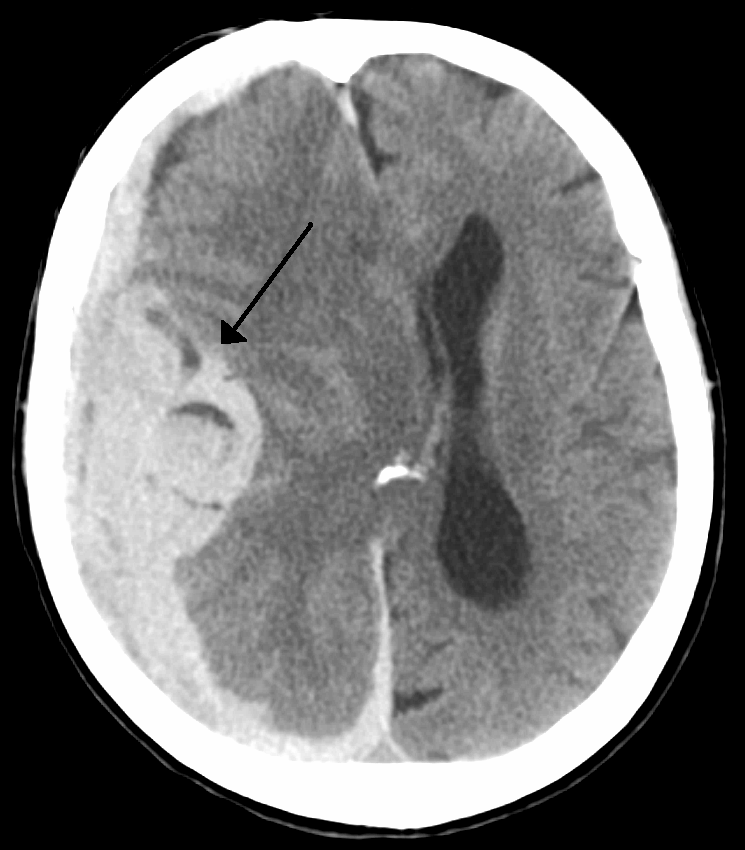

This systematic review and meta-analysis of 4 RCTs found that mortality rates were similar in patients with acute ICH randomized to intensive-BP (SBP <140) versus guideline-BP (SBP <180) control (OR 1.01, 95% CI 0.83-1.23; p = 0.914). The analysis was largely influenced by one RCT, which used an anti-hypertensive agent that is not available in Canada. Lack of clear reporting of clinically important outcomes and baseline clinical characteristics were discussed. JC attendees agreed that there was no practical or clinical advantage in the resource intensive intervention of aggressive BP reduction in acute ICH in the ED.

![By James Heilman, MD (Own work) [CC BY-SA 3.0 (http://creativecommons.org/licenses/by-sa/3.0)], via Wikimedia Commons By James Heilman, MD (Own work) [CC BY-SA 3.0 (http://creativecommons.org/licenses/by-sa/3.0)], via Wikimedia Commons](http://4.bp.blogspot.com/-cZ4kmdSqcMo/Ve2zVLXE9cI/AAAAAAAABVk/Mhbc5JGsgpg/s320/Intracranial_bleed_with_significant_midline_shift.png)